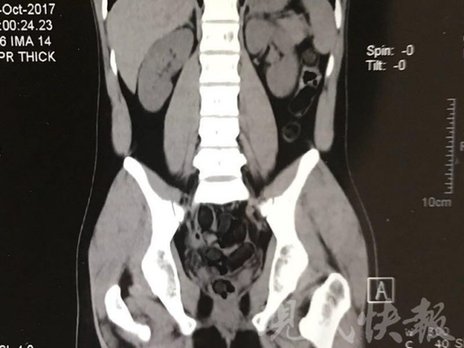

小伙體內(nèi)藏毒300余克 CT掃描圖密密麻麻

由于毒品在體內(nèi)一旦泄露有可能致命,警方第一時間將阿永帶到醫(yī)院進行檢查。CT 掃描的結(jié)果顯示,阿永體內(nèi)布滿了密密麻麻的白色圓柱狀固體,就像一粒粒的蠶蛹。在南京市公安局鼓樓分局二板橋派出所,阿永分四次排出了毒品,毛重369.99克。經(jīng)訊問,阿永交代了自己全部的犯罪事實。目前,阿永已被刑事拘留。